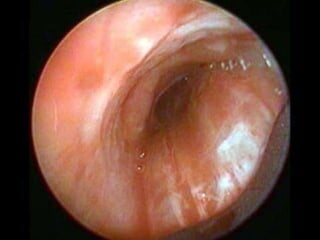

- Tratamiento endoscópicas (Cauterización repetidas, sellantes

de fibrina) habitualmente en fístulas <3mm de diámetro.